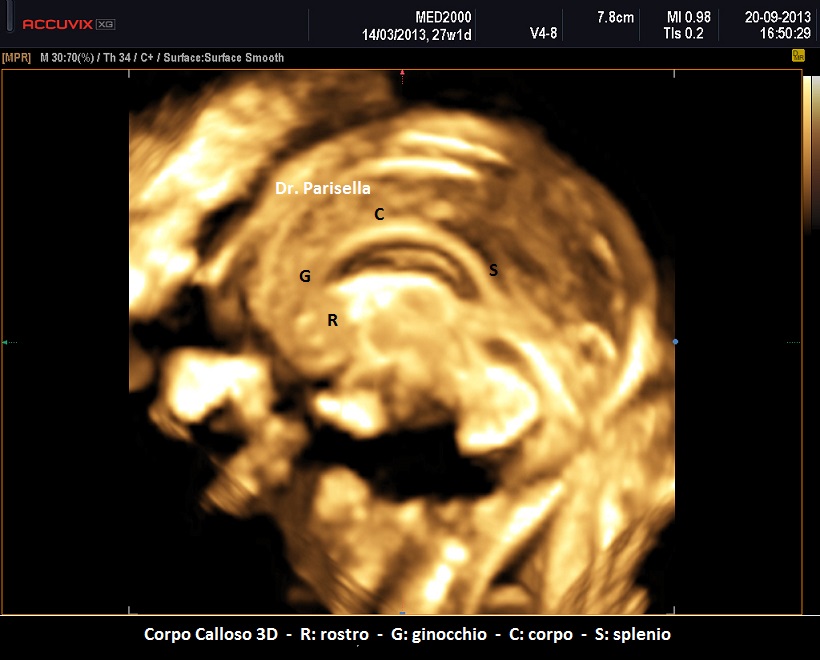

Esso è costituito, in senso antero-posteriore, da quattro porzioni: rostro, ginocchio, corpo, splenio.

La formazione del corpo calloso avviene proprio in senso antero-posteriore, si forma prima il ginocchio e poi il corpo e lo splenio, per cui le anomalie parziali (disgenesia/ipoplasia) interessano la porzione posteriore del corpo e lo splenio.

La visualizzazione del corpo calloso richiede in genere un piano di scansione sagittale e/o quello coronale; può essere di aiuto la tecnica 3D con la quale partendo dalla sezione per la misurazione della circonferenza cranica è possibile ottenere entrambi i piani, sagittale e coronale.